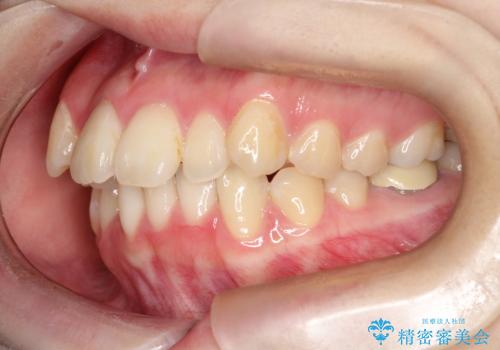

- 「歯のデコボコ、八重歯、口ボコが気になる」を主訴に来院された患者様です。

上下左右4番(4本)の歯を抜歯しワイヤー矯正で治療を行いました。

計4本の抜歯を行い、歯のデコボコと口元がすっきりし、大変ご満足していただけました。